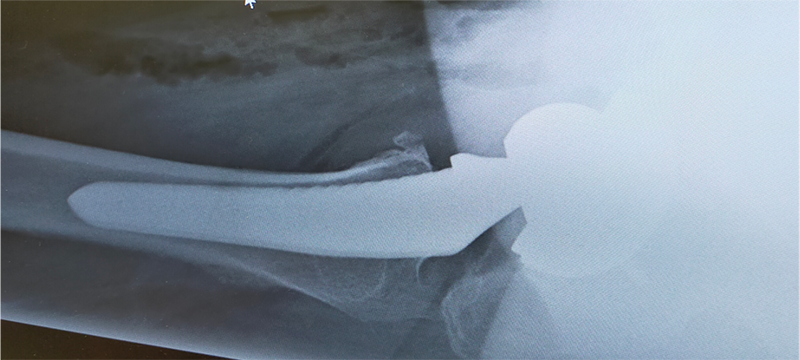

〈手術前のレントゲン〉

〈右股関節のMRI〉

骨頭壊死により、大腿骨の骨が潰れ、非常に疼痛が強く、歩行困難であったために早期の手術を予定。当院にて人工股関節全置換術(THA)を施行。アプローチはAMIS(前方最小侵襲手術)で行い、術中に神経ブロックを行い術後の痛みをコントロールし、術翌日から歩行訓練をはじめ、10日程度で退院となりました。